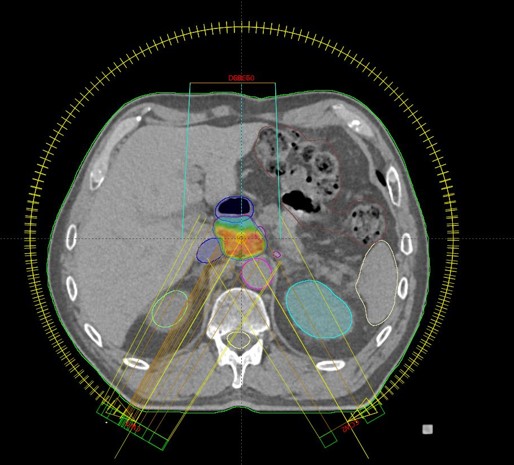

SBRT lymphonodi intraabdominalis (22.11. - 26.11.2021.)